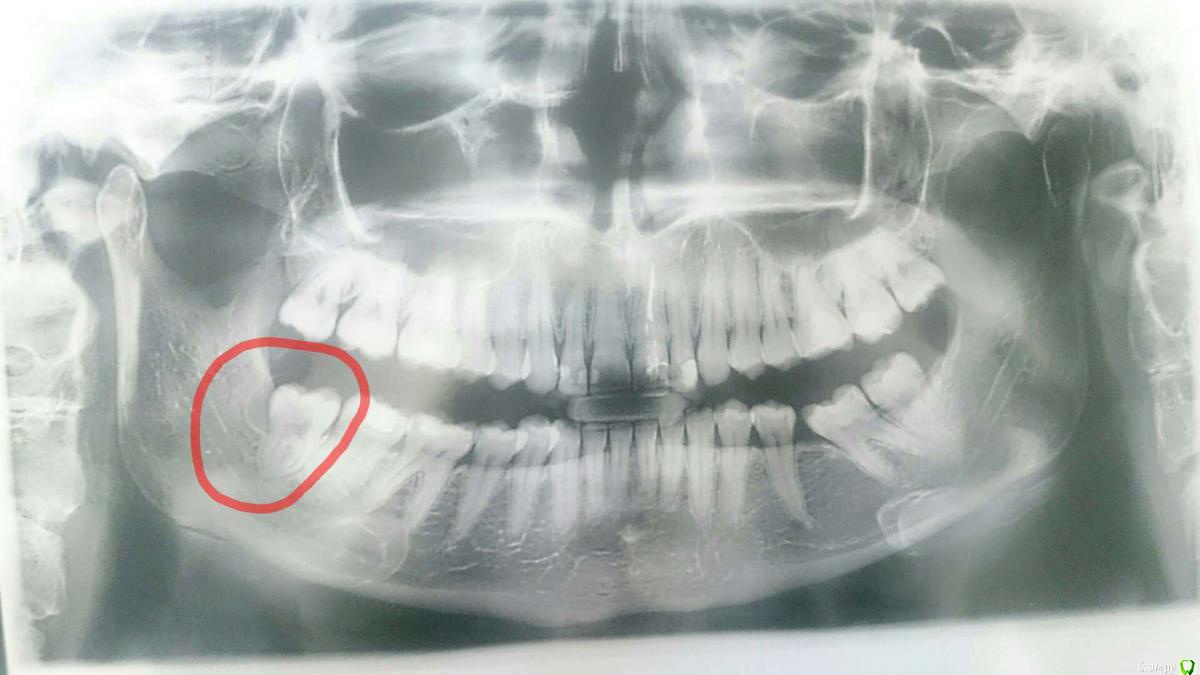

Mariya163 Опубликовано 3 февраля, 2020 Поделиться Опубликовано 3 февраля, 2020 Здравствуйте. Подскажите пожалуйста стоит ли торопиться с удалением зуба мудрости? Полгода назад зуб мудрости начал рости, полностью не может вылезть, хирург сказал что нужно будет удалять со временем. Три дня назад зуб снова начал рости, стало больно глотать, рот полностью больно открыть, на ощупь на шее внизу челюсти под зубом увеличился скорее всего лимфоузел (зуб накрывает десна, его видно не много, как поняла ему не хватает места). Температуры нет. В одной больнице говорили что не нужно ложиться в больницу просто удалят и уйду домой, в другой больнице сказали что необходимо будет лечь в больницу. Лучше обратиться в ту больницу где нужно госпитализироваться? Ссылка на комментарий

Irouil Опубликовано 3 февраля, 2020 Поделиться Опубликовано 3 февраля, 2020 И верхний заодно Ссылка на комментарий

red_butler Опубликовано 4 февраля, 2020 Поделиться Опубликовано 4 февраля, 2020 Подскажите пожалуйста стоит ли торопиться с удалением зуба мудрости? удаляйте сегодня, амбулаторно Ссылка на комментарий